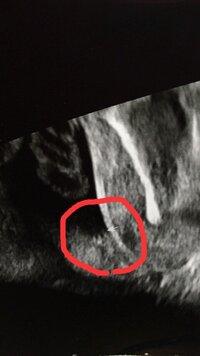

妊娠7ヶ月です おまたの下から撮ったエコーです 男の子か女の子か 妊娠 教えて Goo

こちらのエコーは女の子ですか 男の子ですか 妊娠7ヶ月目 24 Yahoo 知恵袋

ただいま 2人目を妊娠中です 7ヶ月です このエコー写真は女の子か男の子か Yahoo 知恵袋